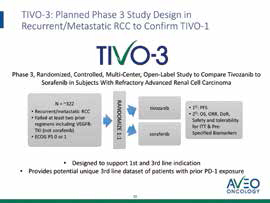

美国克利夫兰医学中心Rini等报告,Tivozanib对比索拉非尼三线或四线治疗转移性肾细胞癌,可改善无进展生存期(PFS),且耐受性更好。(Lancet Oncol. 2019年12月3日在线版)既…